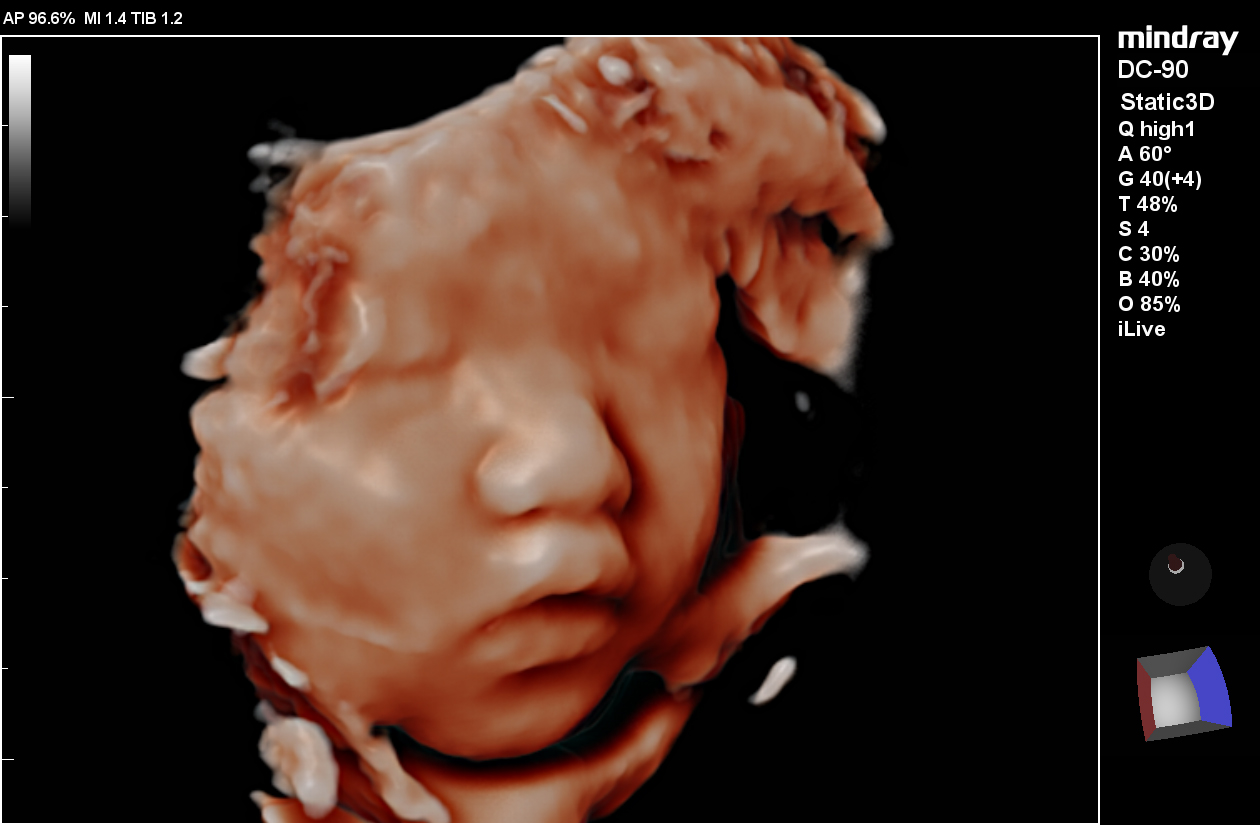

Smart Face

Smart Face provides a fast and intelligent optimization for fetal face with simple one-touch operation. It can immediately remove occlusions such as cord, placenta, uterus, and extremities in the volume data, to generate an optimal view of the fetal face.